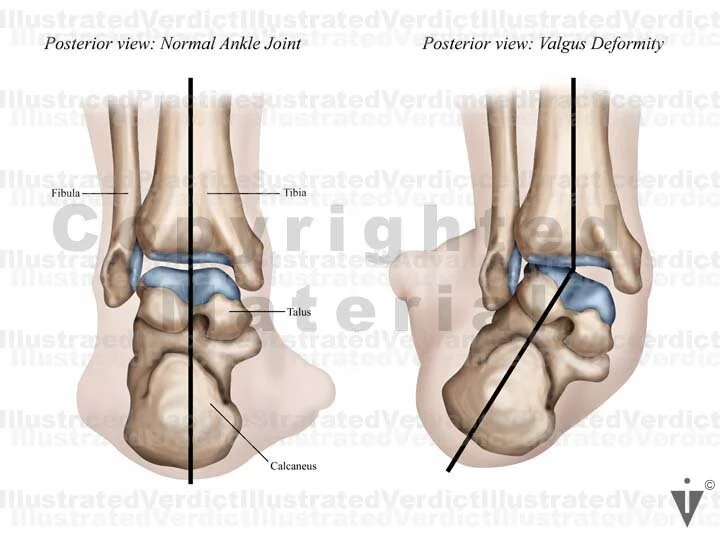

1. Normal alignment of ankle joint (posterior view)

2. Valgus deformity of ankle joint (posterior view)